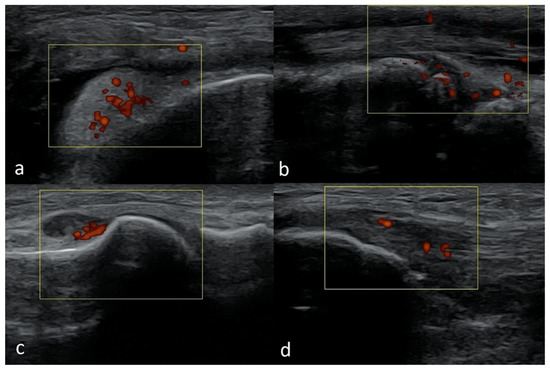

We present basic differences in the musculoskeletal ultrasound examinations between adults and children. Examiners who deal with adults on a daily basis have shared concerns about examining children. Such concerns may arise from the different approach to child ultrasounds, but they also come [...] Read more.

We present basic differences in the musculoskeletal ultrasound examinations between adults and children. Examiners who deal with adults on a daily basis have shared concerns about examining children. Such concerns may arise from the different approach to child ultrasounds, but they also come from differences in anatomical characteristics according to developmental age. We discuss the presence of growth plates, as well as non-mineralized parts of the bones. We also refer to the pathologies most often found in ultrasounds in early developmental stages. In the PubMed database, the set of keywords: “msk ultrasound in children”, “pediatric msk sonoanatomy”, “coxitis fugax”, “pediatric Baker’s cyst”, “Baker’s cyst ultrasonography”, “bone septic necrosis in ultrasonography”, “ultrasonography in juvenile idiopathic arthritis”, and “ultrasonography in juvenile spondyloarthropathies”, was used to identify a total of 1657 results, from which 54 was selected to be included in the article. We discuss the problem of osteochondritis dissecans, Osgood-Schlatter disease, examples of ligament injuries (especially in relation to the knee and ankle joints), exfoliation of growth cartilages, osteochondroma, exudates and inflammations affecting joints, and Baker’s cysts. In this way, we have collected useful information about the most common diseases of the musculoskeletal system in children. Full article